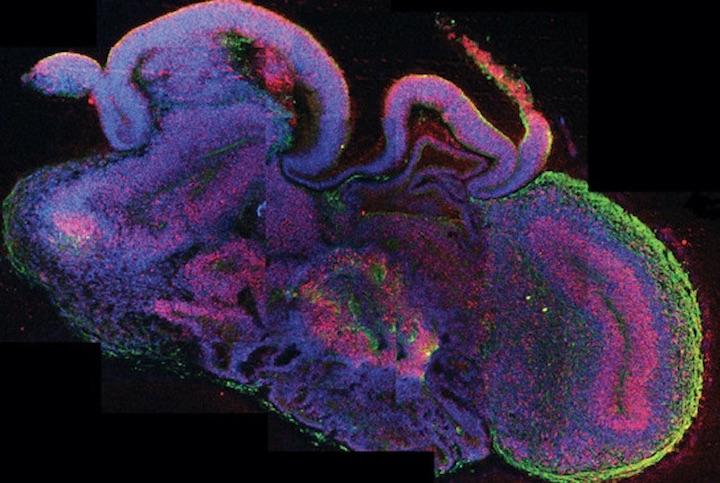

幹細胞を使ってヒトの器官の小さな三次元モデルを生成する技術は、この10年ほどで大幅に進歩した。とりわけ、ヒトの多能性幹細胞から作製する豆粒大の人工脳「脳オルガノイド」は、現代の神経科学で最も注目されている分野のひとつだ。

米ハーバード大学の研究チームが2017年に発表した研究論文では、「脳オルガノイドが大脳皮質ニューロンや網膜細胞などの様々な組織を発達させる」ことが示され、2018年4月にはソーク研究所の研究チームがヒトの脳オルガノイドをマウスの脳に移植したところ、機能的なシナプス結合が認められた。

また、カリフォルニア大学サンディエゴ校の研究チームは2019年8月、「脳オルカノイドからヒトの未熟児と類似した脳波を検出した」との研究結果を発表している。